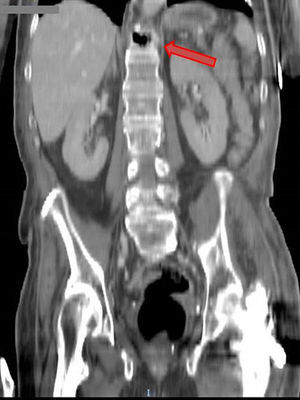

Paciente de 62 años con cuadro de astenia, febrícula y dolor lumbar de un mes de evolución, que ingresa por hipotensión arterial y oligoanuria. En la analítica destaca acidosis metabólica grave y fracaso renal agudo. Se realiza una TAC de abdomen, con presencia de múltiples burbujas aéreas localizadas en retroperitoneo superior, que parecían provenir del espacio interdiscal D10-D11, (figs. 1 y 2). La evolución posterior fue fatal, siendo exitus. El retroneumoperitoneo es un hallazgo radiológico poco frecuente, con sintomatología clínica larvada e inespecífica. La espondilodiscitis es también una infección infrecuente que afecta al cuerpo vertebral y espacios intervertebrales. Un diagnóstico precoz es fundamental para instaurar tratamiento adecuado y mejorar el pronóstico de esta enfermedad.